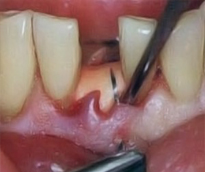

Periodontoloji

Cerrahi Müdahaleler